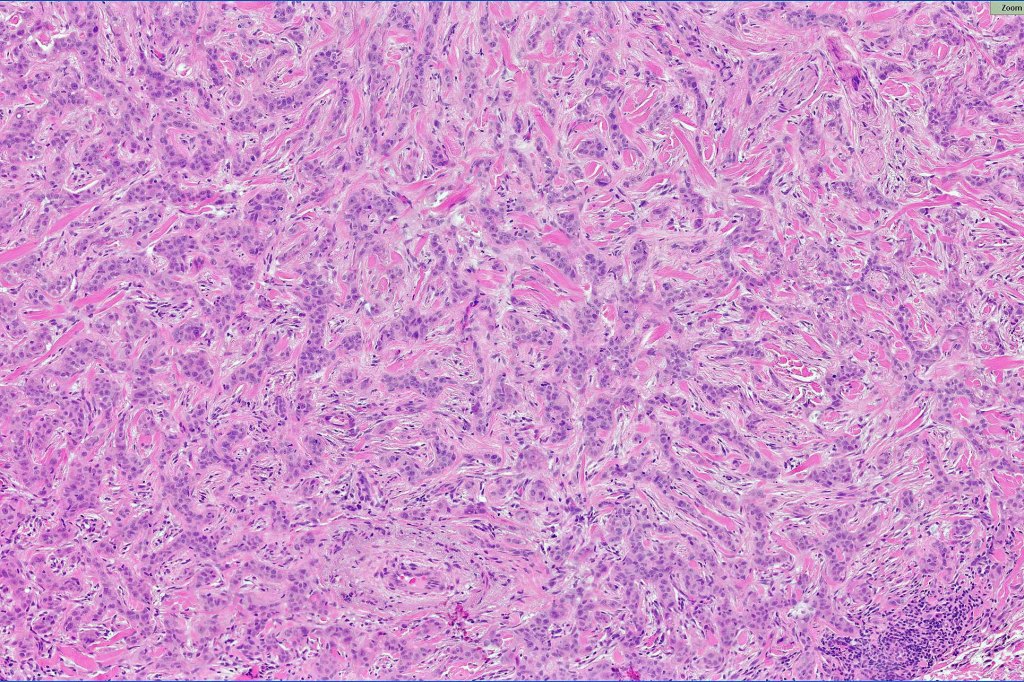

•Ulceration and solar elastosis are common

•Widely infiltrating biphasic tumor

•Superficial SCC

•Adenocarcinoma in deeper reaches

•Often extends to the subcutaneous fat

•Perineural infiltration is commonly seen